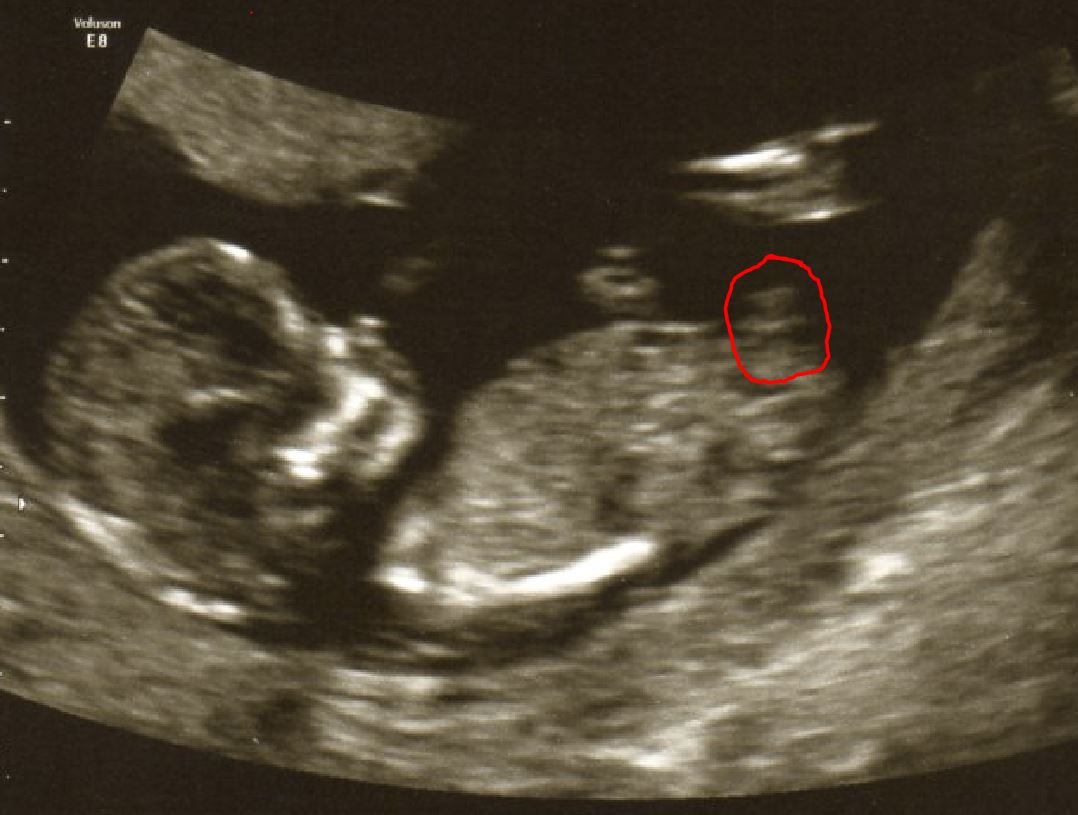

I am new to all this "nub theory" stuff but was wondering am I right in thinking the nub is where I have circled with a red line in the 2 pictures both at 12 weeks + 5 days. To see the picture bigger right click on the picture and select "Open image in new tab" you will see the actual size.

Pic 2

Attachment 13133